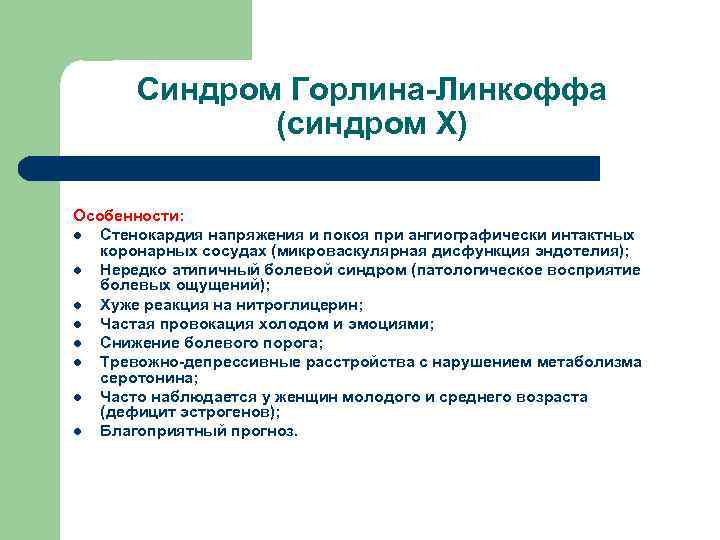

Синдром Горлина-Линкоффа (синдром Х) Особенности: l Стенокардия напряжения и покоя при ангиографически интактных коронарных сосудах (микроваскулярная дисфункция эндотелия); l Нередко атипичный болевой синдром (патологическое восприятие болевых ощущений); l Хуже реакция на нитроглицерин; l Частая провокация холодом и эмоциями; l Снижение болевого порога; l Тревожно-депрессивные расстройства с нарушением метаболизма серотонина; l Часто наблюдается у женщин молодого и среднего возраста (дефицит эстрогенов); l Благоприятный прогноз.